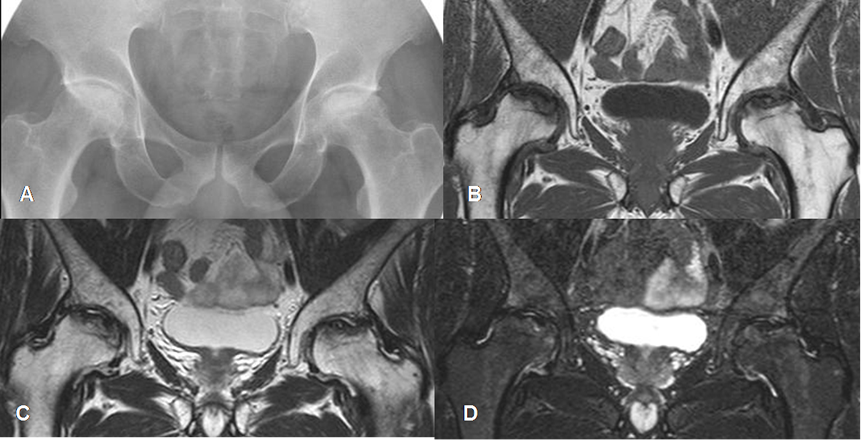

Fig 84 B. Osteonecrosis. Clase D.

A: Rx AP. Aumento de la densidad en el borde superior de las cabezas femorales, por osteonecrosis de evolución crónica.

B: RM coronal en T1, C: RM coronal en T2 y D: RM coronal en STIR. La parte superior de las cabezas es hipointensa en todas las secuencias, por fibrosis, secundaria a osteonecrosis crónica.